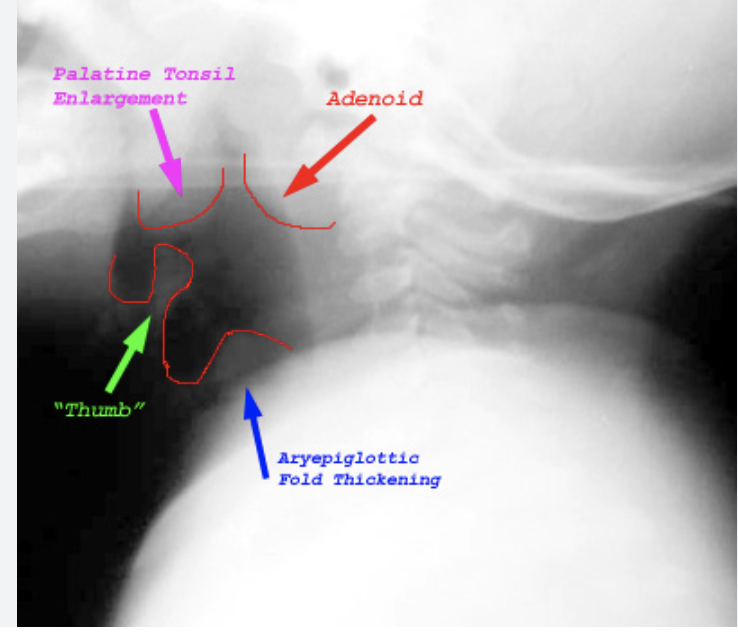

1 - Lateral neck radiograph (‘thumb sign’)

4 - Clinical diagnosis

Flexible fiberoptic laryngoscopy (ENT only) will show a cherry red epiglottis